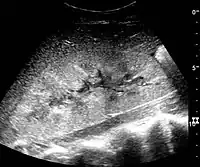

Cystic renal masses

Masses are seen as a distortion of the normal renal architecture. Most renal masses are simple cortical renal cysts with a round appearance and a smooth thin capsule encompassing anechoic fluid. The incidence increases with age, as at least 50% of people above the age of 50 have a simple cyst in one of the kidneys. Cysts cause posterior enhancement as a consequence of reduced attenuation of the ultrasound within the cyst fluid (Figure 5). The simple cyst is a benign lesion, which does not require further evaluation.[1]

Figure 5. Simple renal cyst with posterior enhancement in an adult kidney. Measurement of kidney length on the US image is illustrated by '+' and a dashed line.[1]